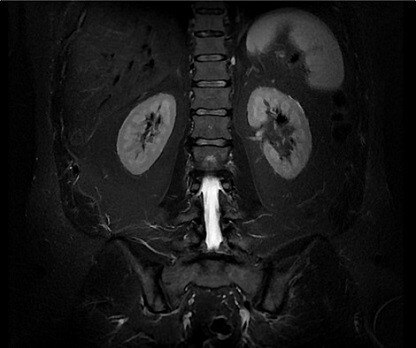

With BodyWorks, we address one of the fastest growing areas in MR. This all-inclusive library allows you to image abdominal and pelvic anatomy with user flexibility to adapt to different patient types.

Auto Navigator is GE's solution to combat respiratory motion in abdominal imaging. This free-breathing approach is compatible with multiple pulse sequences including diffusion, PROPELLER MB, MRCP and dynamic T1 imaging.CVWorks

The four images demonstrate dynamic T1 imaging with PB Navigator, which enables the patient to breathe freely while capturing contrast in fast temporal phases. Whole spine evaluation can be obtained simply with routine T2 frFSE imaging.